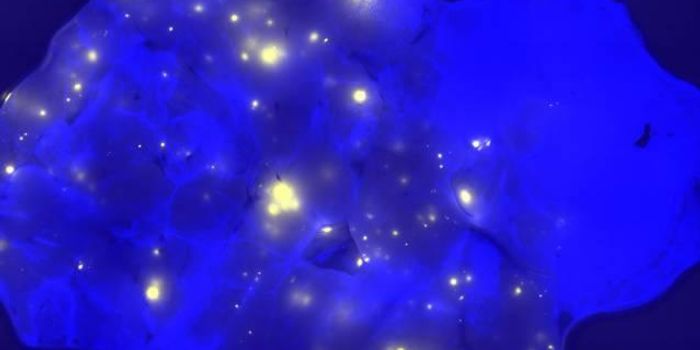

OCT 10, 2016Clinical & Molecular DXA new technique under Phase 1 clinical trial gave surgeons the ability to see a brain tumor glow like they’ve neve ...